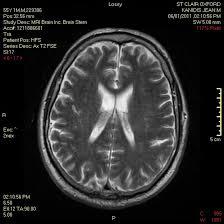

This course is designed for Physicians and Advanced Practice Clinicians who want to improve their skills in evaluating, diagnosing, and managing complex stroke cases. Participants will review key imaging modalities, including CT, MRI, and other neuroimaging techniques, and learn how to apply them in stroke diagnosis and treatment. Through case studies, participants will review how to interpret imaging and making informed clinical decisions. This course aims to improve neurological knowledge, competency, and clinical performance in stroke care.

1. Improve interpretation of MRI findings

2. Correlate neuroimaging to patient presentation

3. Review common imaging nomenclature and terminology